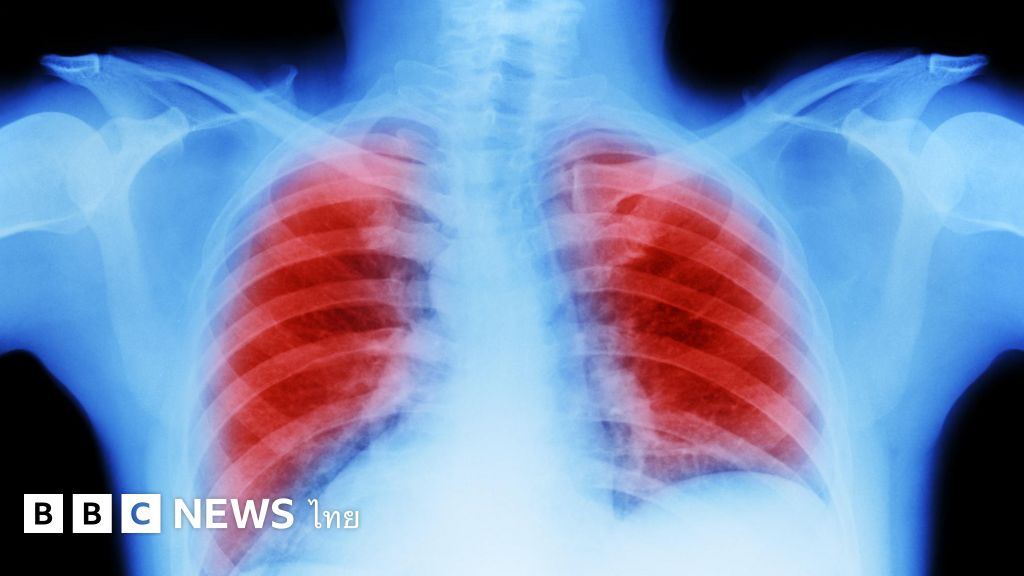

Lung cancer Scientists have discovered that How does air pollution lead to cancer? BBC News Does Air Pollution Cause Cancer Different types of air pollution have been linked to a variety of cancers. air pollution could cause lung cancer not by mutating dna, but by creating an inflamed environment that encourages proliferation. air pollution is associated with the development of lung cancer. Learn about different air pollutants, how they affect you, and how you can protect yourself. . Does Air Pollution Cause Cancer.